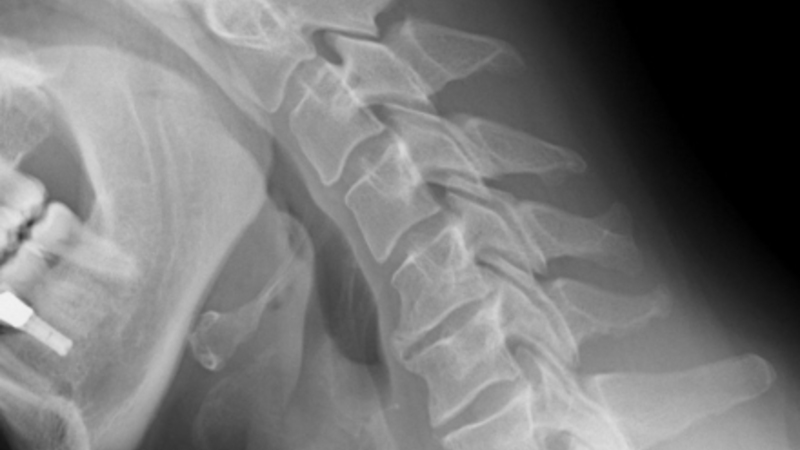

Costa del Sol sygehuset i Marbella er blevet pålagt at betale erstatning på 79.564 euro til en patient, der blev sendt hjem med en brækket nakke.

Men smerterne fortsatte, og på et tidspunkt kunne manden slet ikke bevæge den ene arm. En scanning på en privatklinik afslørede, at der var et brud i en halshvirvel efter slaget, og manden blev sendt til undersøgelse på Carlos Haya Sygehuset i Málaga, som bekræftede at, manden havde brækket nakken.